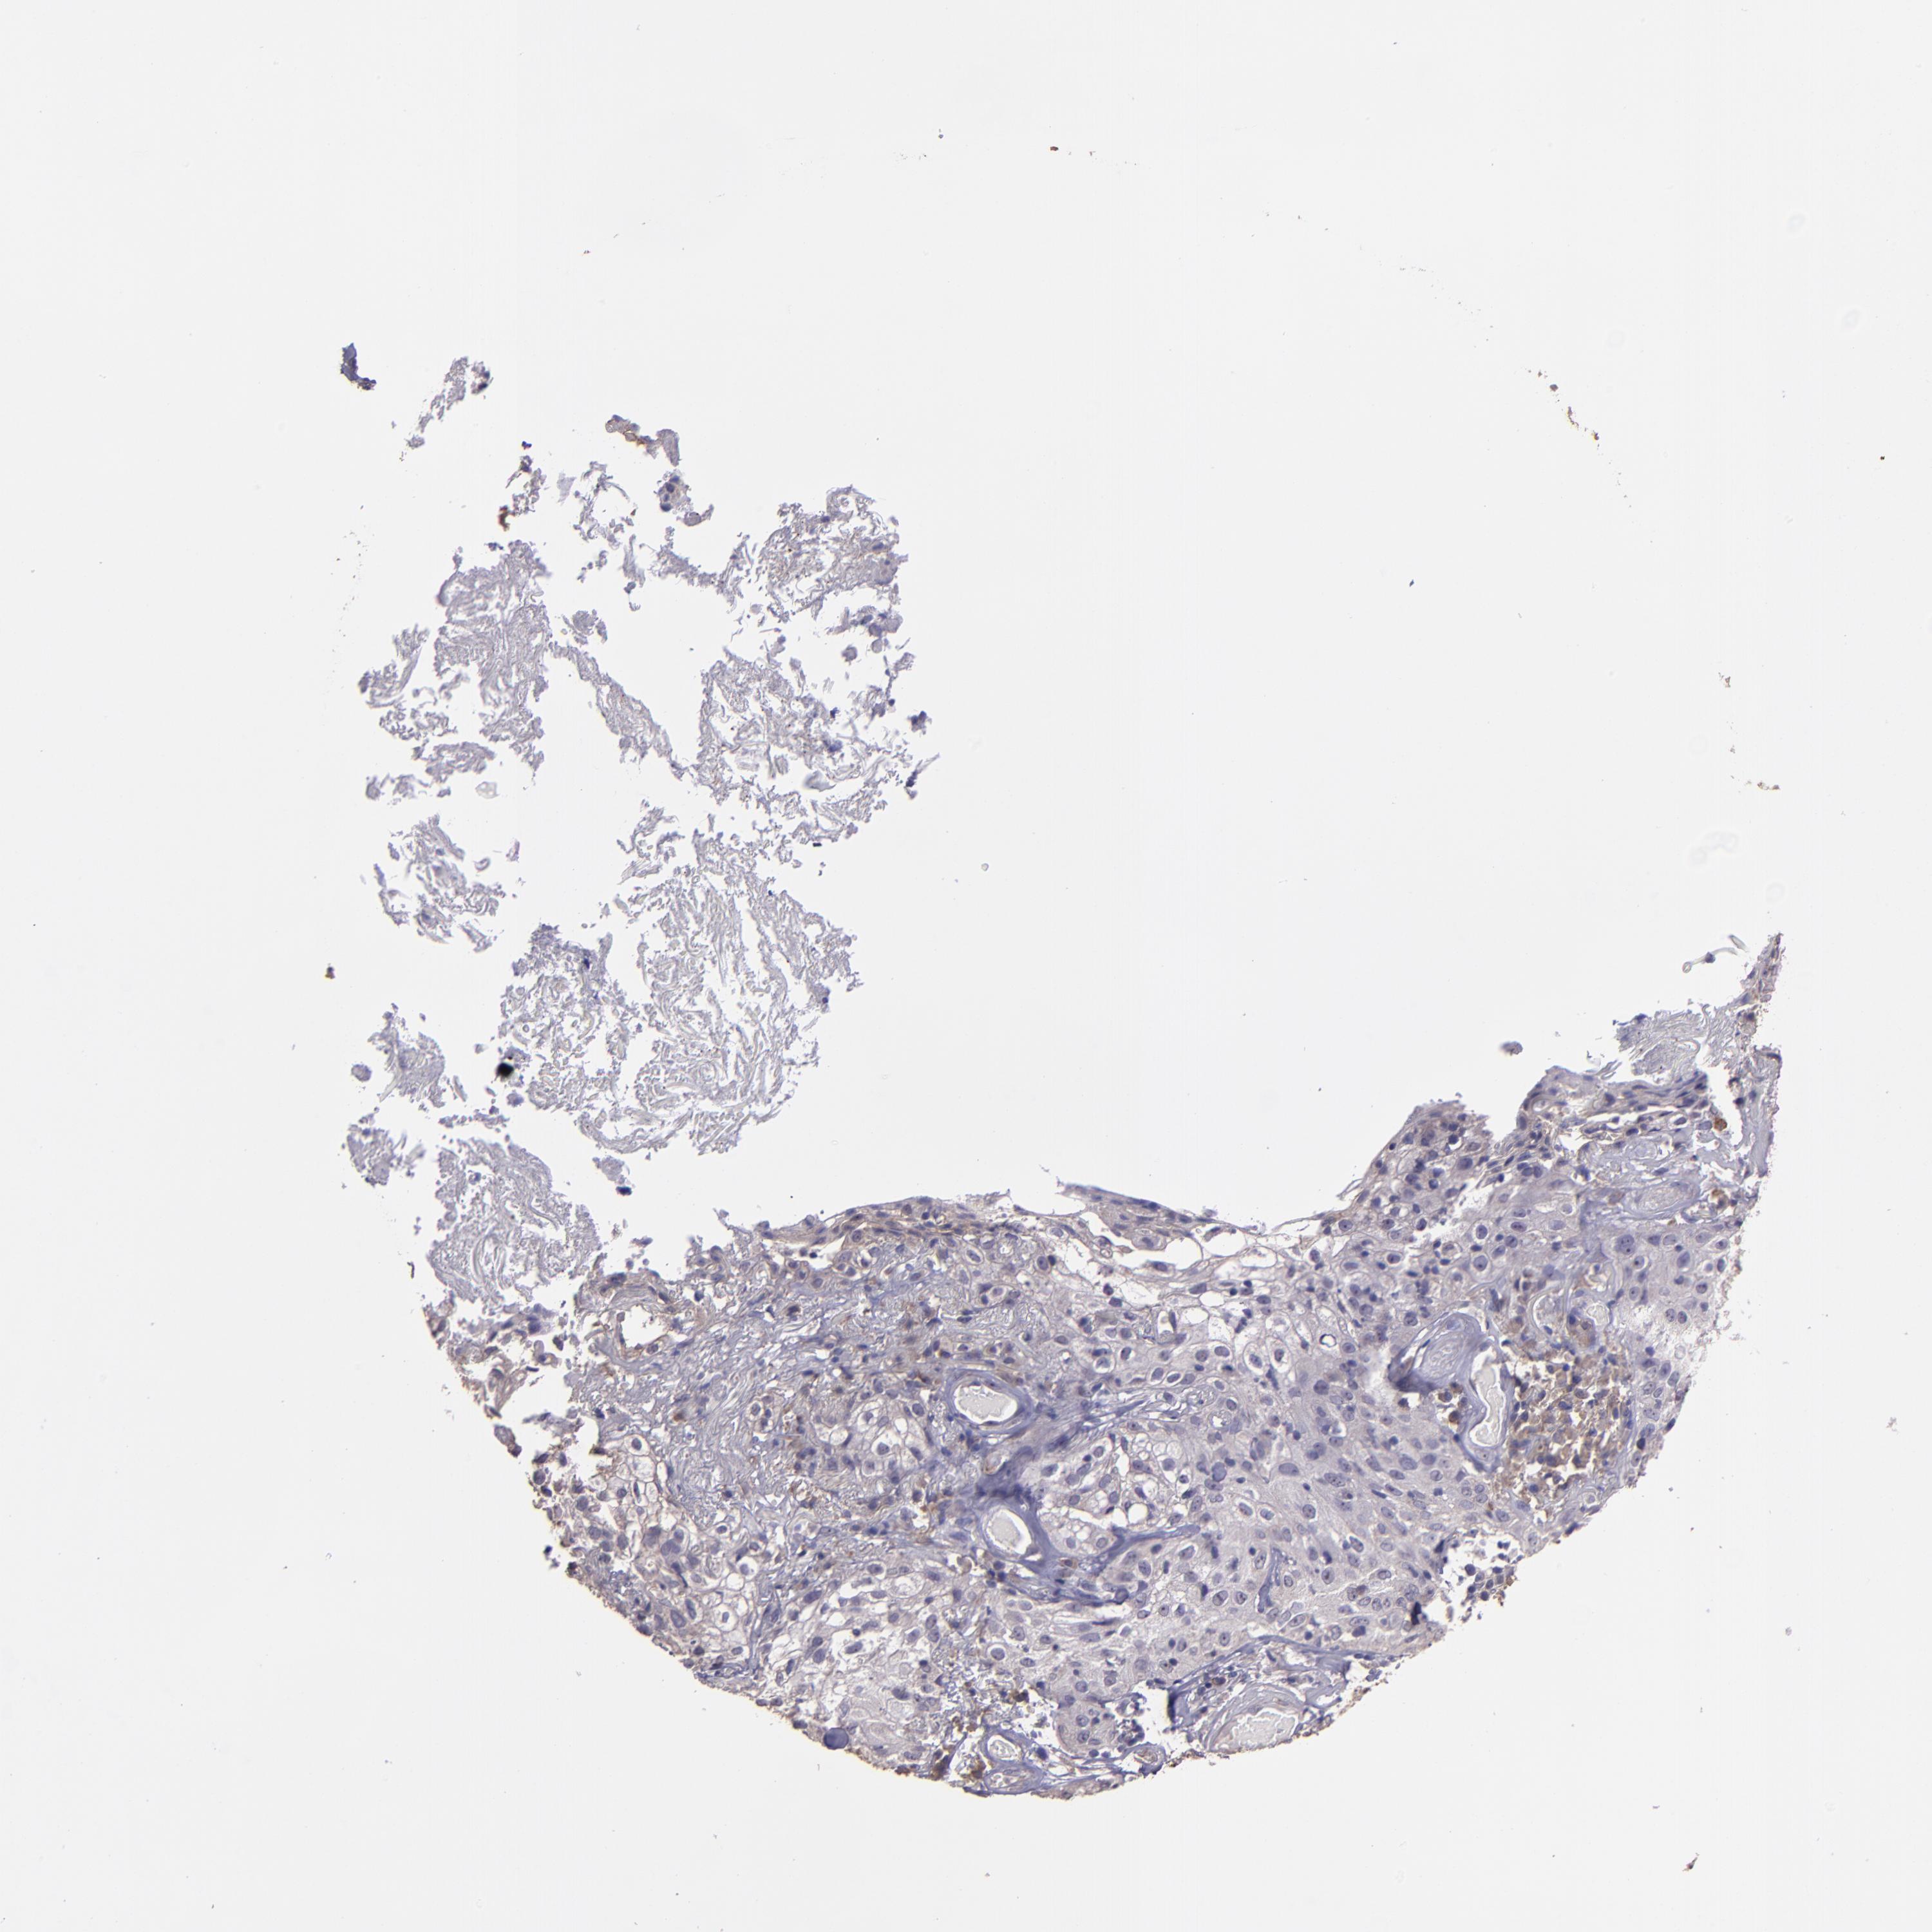

SKIN CANCER - Protein expressioni

A mouse-over function shows sample information and annotation data. Click on an image to view it in a full screen mode. Samples can be filtered based on level of antibody staining by selecting one or several of the following categories: high, medium, low and not detected. The assay and annotation is described here.

Each image is clickable and will lead to virtual microscopy that enables deeper exploration of all samples and also displays staining intensity scores, fraction scores and subcellular localization as well as patient and tissue information for each sample.

Antibody HPA001667

Squamous cell carcinoma, NOS